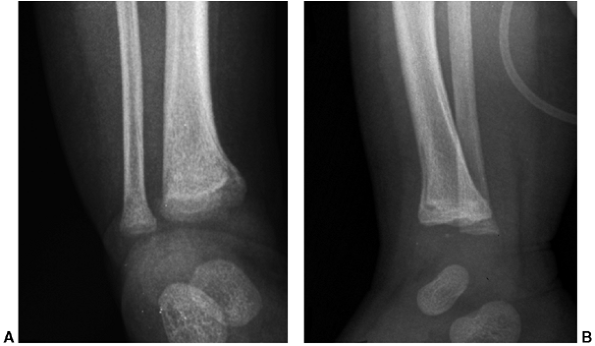

being inflicted by abusive trauma. Metaphyseal “bucket-handle” or

“corner” fractures often form the basis for the diagnosis of abuse (Fig. 34.1) and are considered pathognomonic for abusive trauma. They have highly distinctive radiographic characteristics (32)

that result from the isolation of a mineralized disc (or a part

thereof) that can be seen radiographically. Depending on its size and

the orientation and angle of the radiograph, one will see a

bucket-handle lesion, corner fracture, or metaphyseal lucency. The

metaphyseal lesion may be difficult to identify on plain radiographs.

![]() |

Figure 34.1 Classic metaphyseal lesion of the distal tibia in a 2-week-old infant. A: Anteroposterior ankle. (B:) Lateral ankle. This finding is pathognomonic for child abuse.